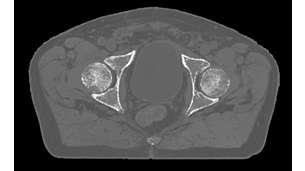

MRCAT Prostate + Auto-Contouring

As a plug-in clinical application to Ingenia MR-RT, MRCAT Prostate + Auto-Contouring provides attenuation maps and automated, MR-based contours of prostate and organs at risk in as little as 20 minutes – all in a repeatable ‘one-click’ workflow.

MRCAT Pelvis

MRCAT Pelvis lets you plan radiation therapy using MRI as a single modality solution. Within just one MR exam, MRCAT Pelvis provides excellent soft-tissue contrast for target and OAR delineation, and continuous Hounsfield units for dose calculations. MRCAT (MR for Calculating ATtenuation) data can be used for export to treatment planning systems for CT-equivalent** dose calculations. In addition, MR-based imaging enables CBCT-based positioning based on soft-tissue contrast with the look and feel of CT.